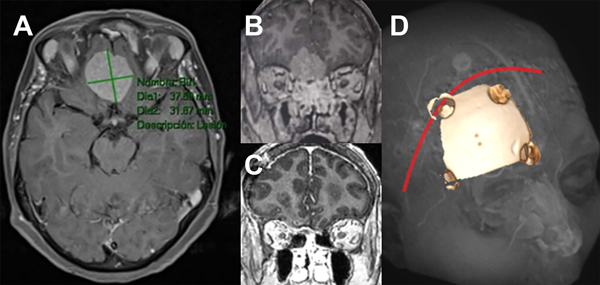

Se analizaron características epidemiológicas y clínicas del paciente, y características del tumor ya sea localización, tamaño, imagenológicas y si tiene embolización previa o no. El grado de resección se midió con la clasificación de Simpson tradicional y también se dividió en resección total (Simpson I, II y III) y subtotal (Simpson IV y V) (Figura 1).

Figura 1: Imágenes representativas de paciente operado de meningioma de base de cráneo anterior de surco olfatorio. A: secuencia T1 con contraste de resonancia magnética, corte axial. B: Misma lesión corte coronal C: corte coronal de imagen posoperatoria. D: abordaje y craneotomía realizada.